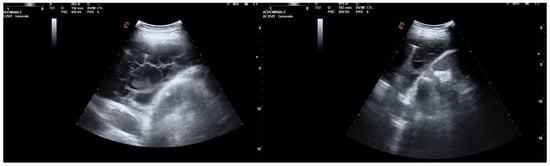

A 26-year-old man was admitted to our hospital for worsening dyspnea at rest and pain in the right hemithorax. The patient complained of a fever (39.5 °C) and productive cough for about 1 week, with mild hemoptysis in the days prior. His medical history included bilateral bronchiectasis and bronchial asthma, for which he received inhalation therapy with a long-acting antimuscarinic agent, long-acting bronchodilator, and inhaled corticosteroid. He had no family history of respiratory disease and had been tested for cystic fibrosis transmembrane regulator (CFTR) gene mutations, with negative results. The patient did not smoke cigarettes, drink alcohol, or use recreational drugs. An arterial blood gas (ABG) analysis showed acute hypoxemic normocapnic respiratory failure; therefore, oxygen therapy with a 28% FiO2 via a Venturi mask was administered. Chest radiography showed an area of opacification at the right base. Empiric antibiotic therapy with 12 mg/kg teicoplanine (Q8H) and 4.5 g piperacillin/tazobactam (Q6H) was then started on suspicion of community-acquired pneumonia. Blood tests upon his admission showed leukocytosis (WBC 18.84 × 109 cells/L) with predominant neutrophils (14.5 × 109 cells/L). Legionella and pneumococcal antigens in his urine were negative. Blood cultures after 72 h were negative. Chest ultrasonography revealed a multiloculated effusion (Figure 1).

Figure 1. Chest US at admission. Multiloculated pleural effusion.